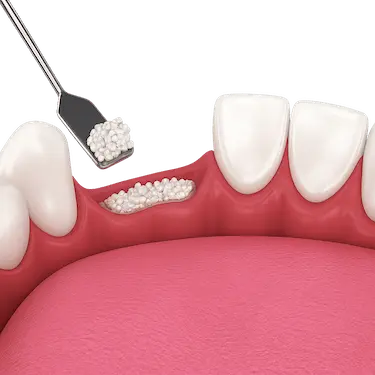

El material de injerto suele presentarse en forma de partículas biocompatibles que, al integrarse, favorecen la regeneración del hueso maxilar.

La regeneración ósea proporciona una buena sujeción, aumentando la anchura y la altura del hueso de manera que el implante dental pueda estar completamente anclado sin movimiento.